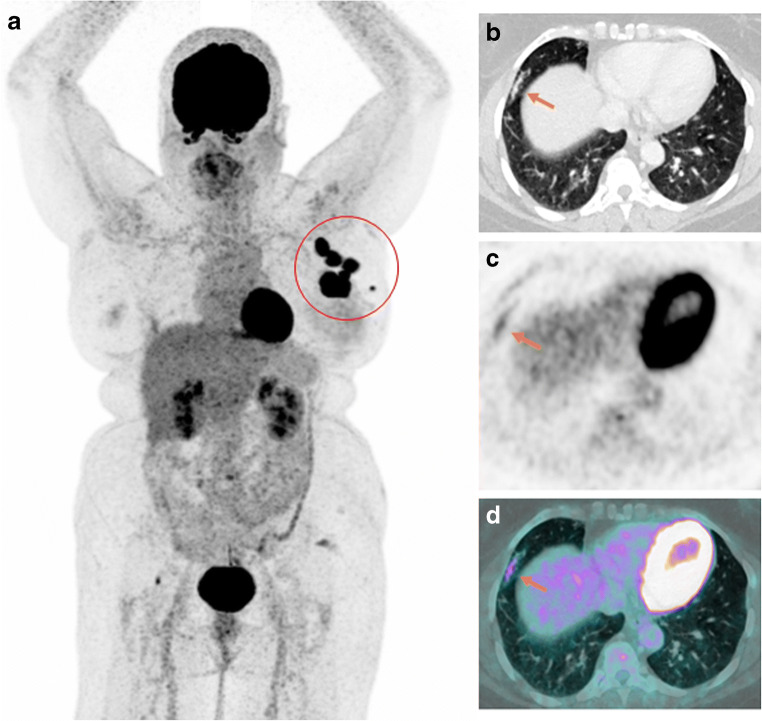

Case 1

A 63-year-old woman underwent 18F-FDG PET/CT for staging of locally advanced triple negative breast cancer. PET/CT showed a FDG-avid left breast mass and positive axillary lymph nodes. Additionally, focal GGOs with partial consolidation, ill-defined, and subpleural distribution in the middle lobe with FDG uptake were visualized (Fig. 1).

Fig. 1.

Maximum intensity projection (MIP) (a) showing hypermetabolic left breast mass and axillary lymph nodes (red circle). Subsequent axial CT (b), PET (c), and fused PET/CT images (d) showing focal GGOs with partial consolidation in the middle lobe, with moderate 18F-FDG uptake (orange arrows). SUVmax 3.06